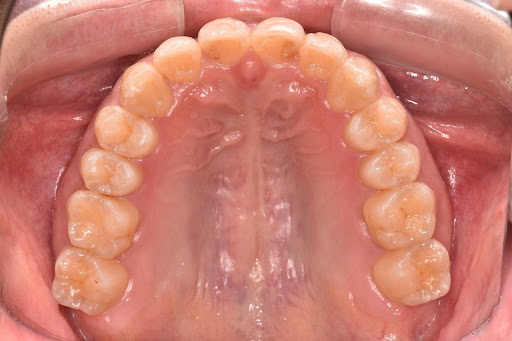

【症例写真】豊富な経験に基づき、歯の重なりやアーチの形状を美しく改善します。

After